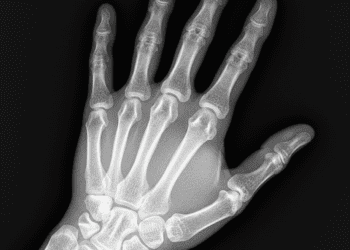

Leia MaisDetailsA radiografia é um dos pilares fundamentais da prática odontológica moderna, desempenhando um papel crucial na identificação de condições que...

Leia MaisDetailsA radiologia dentro da odontologia deixou de ser apenas um recurso complementar e passou a ocupar um papel central no...

Leia MaisDetailsOs aparelhos de raios X odontológicos são ferramentas fundamentais na prática clínica, permitindo a obtenção de imagens precisas da estrutura...